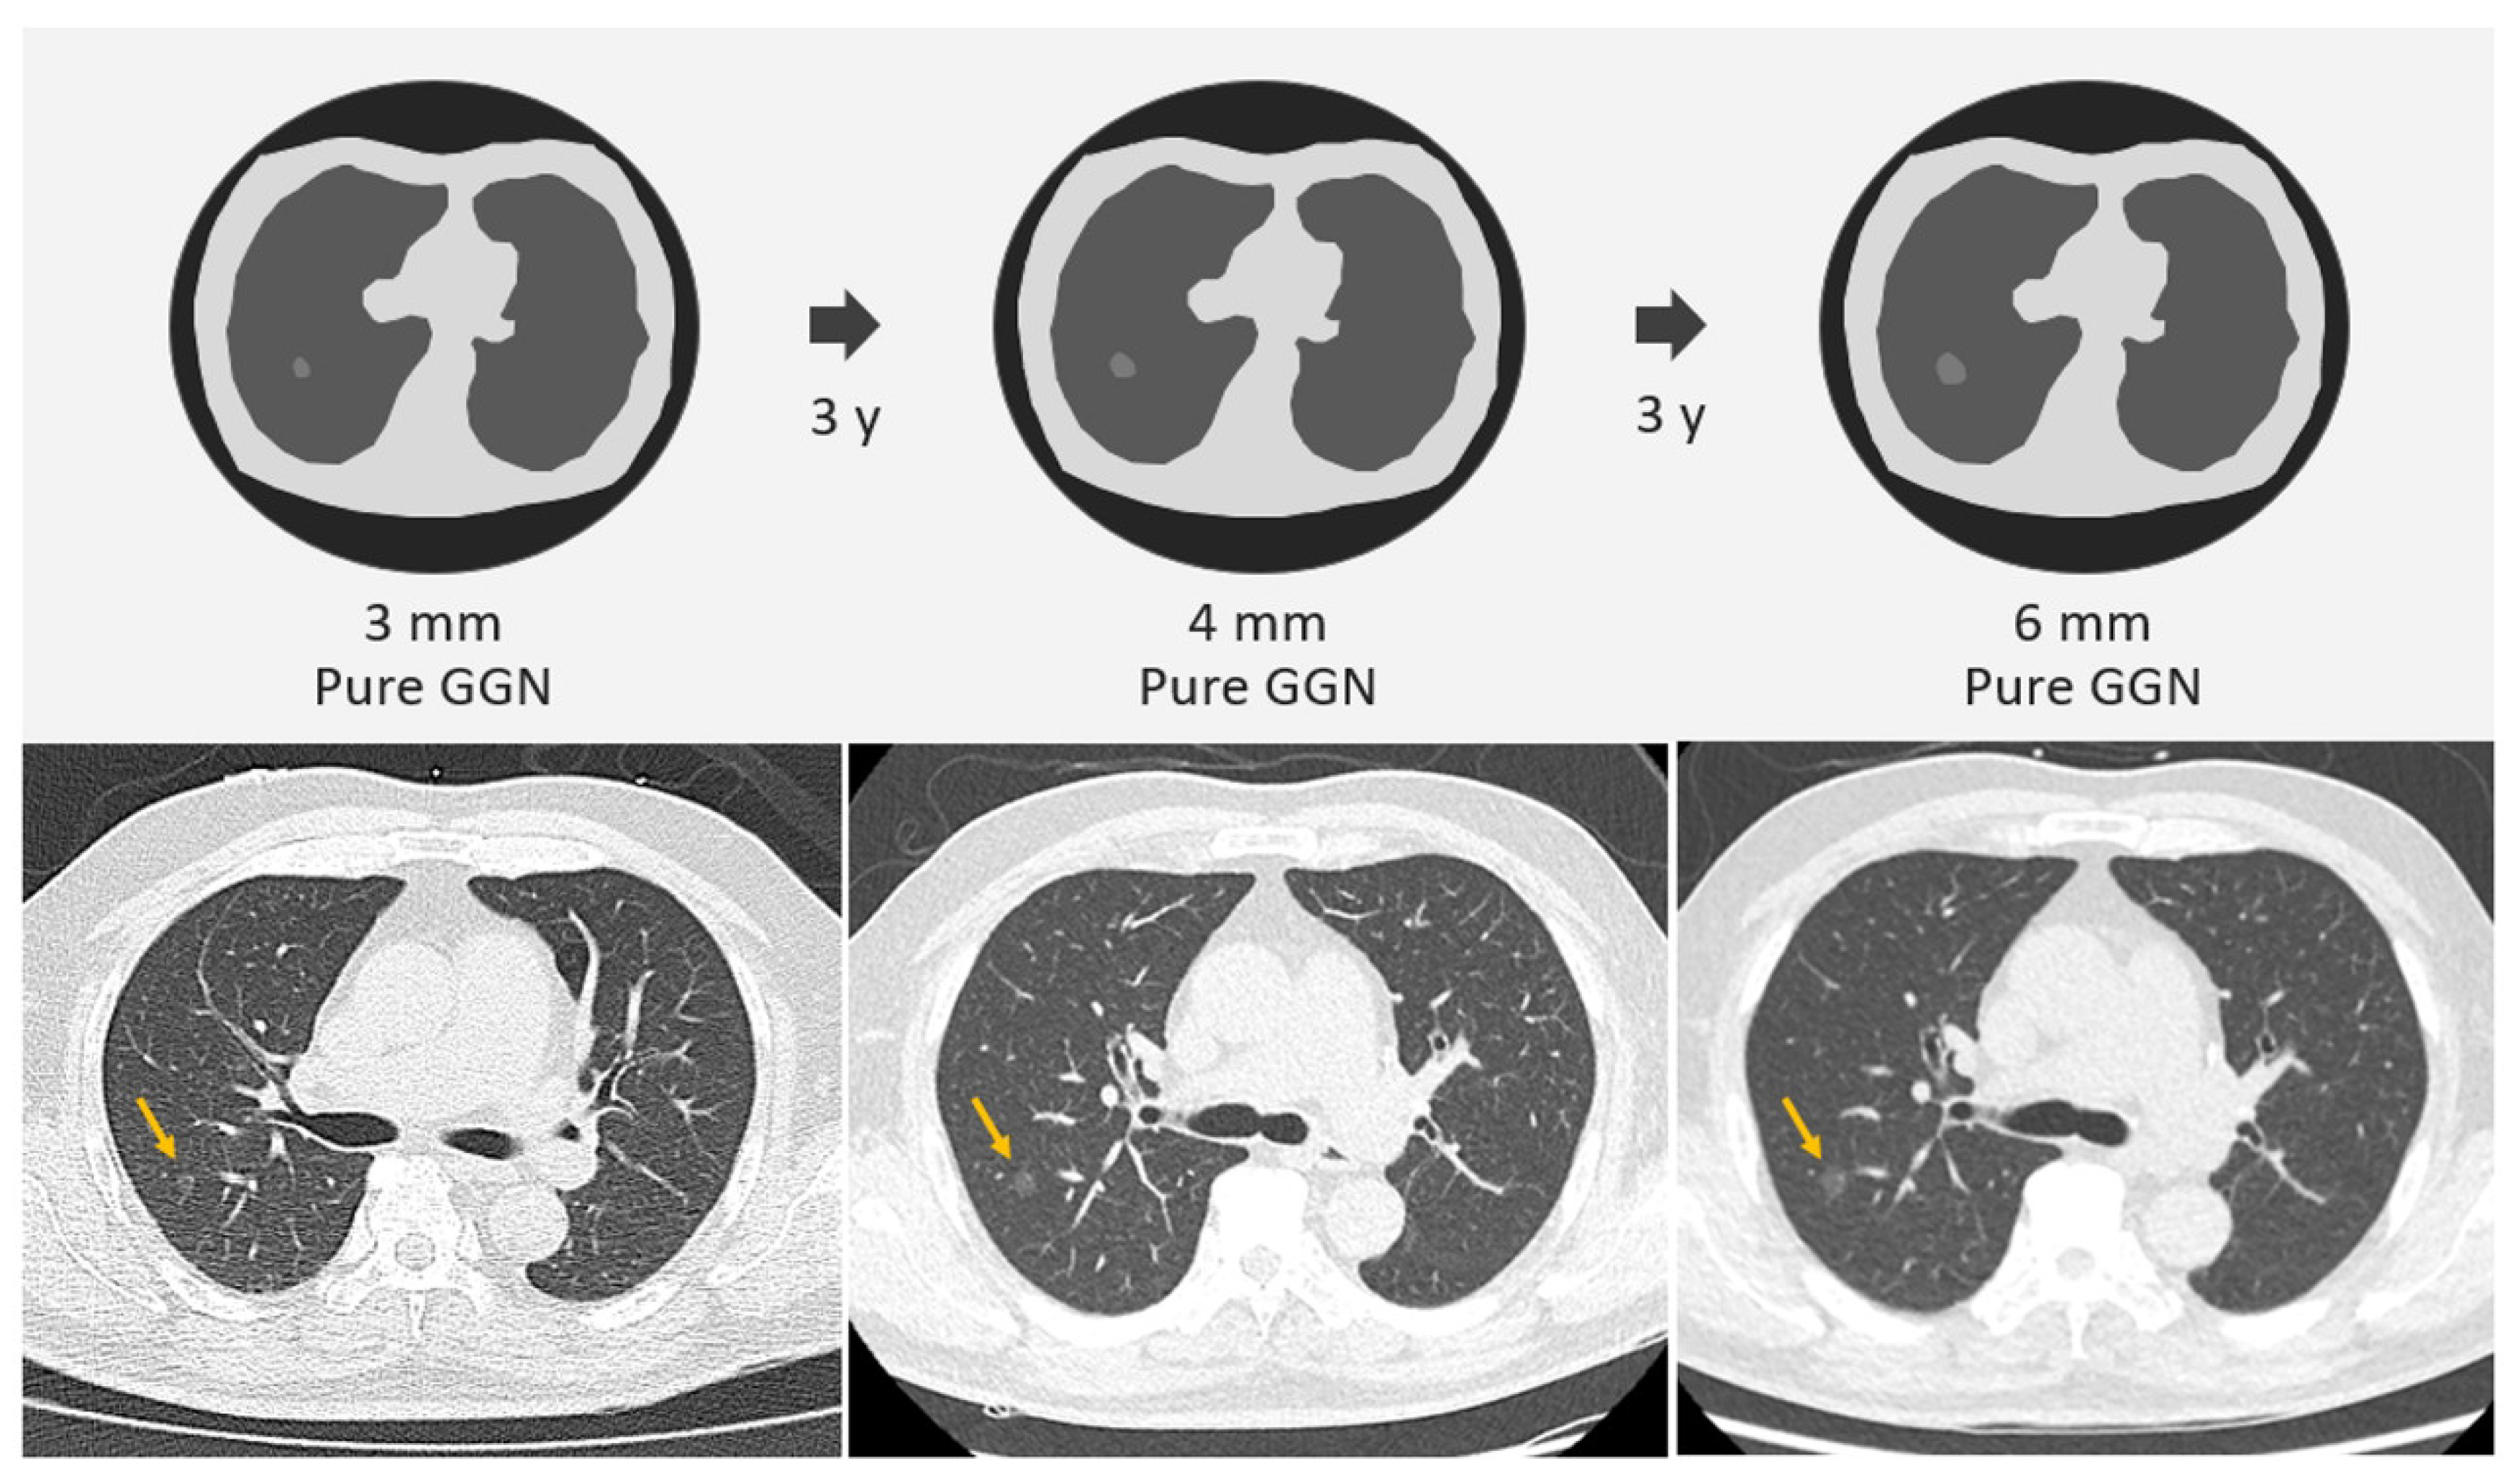

2.1. SSNs Interval Growth with an Increase of ≥2 mm

- Tang, E.-K.; Chen, C.-S.; Wu, C.C.; Wu, M.-T.; Yang, T.-L.; Liang, H.-L.; Hsu, H.-T.; Wu, F.-Z. Natural History of Persistent Pulmonary Subsolid Nodules: Long-Term Observation of Different Interval Growth. Heart Lung Circ. 2019, 28, 1747–1754. [Google Scholar] [CrossRef]

- Kakinuma, R.; Noguchi, M.; Ashizawa, K.; Kuriyama, K.; Maeshima, A.M.; Koizumi, N.; Kondo, T.; Matsuguma, H.; Nitta, N.; Ohmatsu, H.; et al. Natural History of Pulmonary Subsolid Nodules: A Prospective Multicenter Study. J. Thorac. Oncol. 2016, 11, 1012–1028. [Google Scholar] [CrossRef] [PubMed]

- Wu, L.; Gao, C.; Kong, N.; Lou, X.; Xu, M. The long-term course of subsolid nodules and predictors of interval growth on chest CT: A systematic review and meta-analysis. Eur. Radiol. 2022, 33, 2075–2088. [Google Scholar] [CrossRef]

- Lee, H.W.; Jin, K.N.; Lee, J.K.; Kim, D.K.; Chung, H.S.; Heo, E.Y.; Choi, S.H. Long-Term Follow-Up of Ground-Glass Nodules After 5 Years of Stability. J. Thorac. Oncol. 2019, 14, 1370–1377. [Google Scholar] [CrossRef]